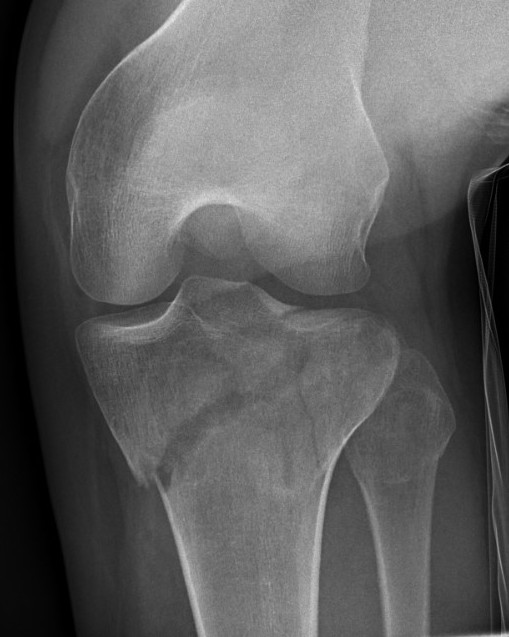

I. Lateral Spilt

- seen in young patient

- lateral meniscus can be incarcerated in fracture

II. Lateral Split Depression

- often seen in young patients with high energy injuries

- vary in severity

III. Lateral Depression

- central depression usually seen in elderly